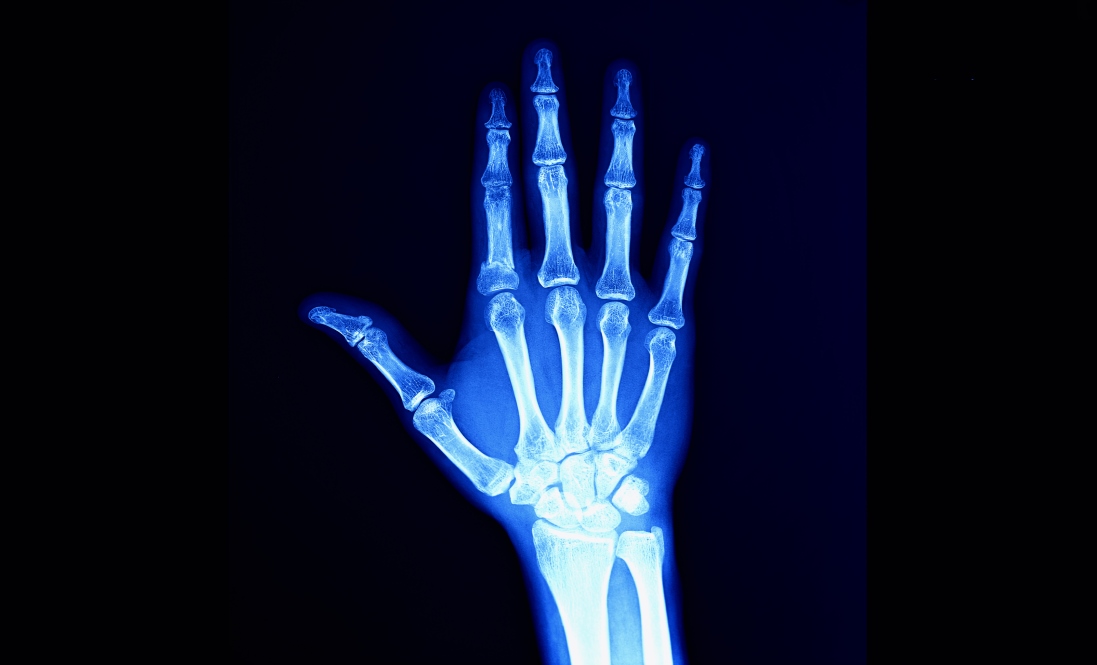

Wrist anatomy

Firstly, we will look at the anatomy of the wrist, to understand how osteoarthritis affects it.

The wrist is a complex joint, connecting the hand to the forearm. The hand is formed from 14 phalanges (referring to the digits of each finger), connected to 5 metacarpal bones, which then connect to the 8 carpal bones of the wrist. The 8 carpal bones are:

The carpal bones are grouped, forming the carpal tunnel, and connect the forearm bones, the radius and the ulna, to the wrist.

Diagnosing wrist osteoarthritis

Wrist osteoarthritis can often be easily diagnosed simply through the presentation of symptoms. A clinician may be able to diagnose osteoarthritis if you are experiencing pain, swelling and stiffness at your wrist joint, however, an X-ray may also be helpful to show exactly where the degenerative joint is and its progression. In more complex cases, magnetic resonance imaging (MRI) may be used to show a more detailed picture of the joint, including the cartilage and soft tissue.